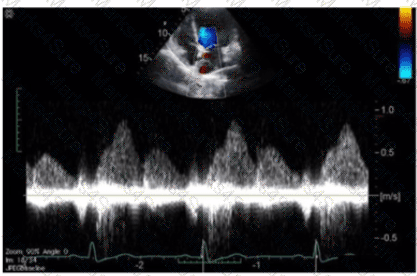

Which maneuver aids in uncovering potential diastolic dysfunction while performing pulsed wave Doppler of the mitral valve?